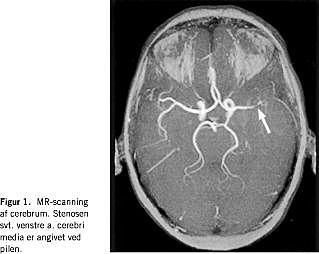

En 42-årig, tidligere rask kvinde af dansk afstamning blev indlagt på mistanke om apopleksi. Forud for indlæggelsen havde patienten haft hovedpine og tilbagevendende tilfælde af 1-2 minutters varighed med følelsesløshed og tyngdefornemmelse i de højresidige ekstremiteter, efterfulgt af nedsat kraft og styringsbesvær. Der var ingen familiære dispositioner for tromboemboliske sygdomme. Tobaksforbruget var på 10-15 cigaretter daglig. Hun anvendte ikke hormonel antikonception. Objektivt fandtes højresidig central facialis parese samt nedsat kraft i højre underekstremitet. Der påvistes leukocytose, uden C-reaktivt protein eller sænkningsreaktionsforhøjelse. En magnetisk resonans (MR)-skanning af cerebrum, et elektroencefalogram og en spinalvæskeundersøgelse viste alle normale forhold, og efter 12 dages indlæggelse blev patienten udskrevet. Hun blev genindlagt fem uger senere med ekspressiv afasi og kramper i begge underekstremiteter. En computertomografi af cerebrum viste infarkt ved venstre capsula interna. En ultralydundersøgelse af halskar og hjerte viste, at de var uden embolikilder. På mistanke om postinfarkt epilepsi blev patienten sat i behandling med oxcarbazepin. I efterforløbet fik hun urtikaria og Coombs negative hæmolyse (medikamentelt betinget?). oxcarbazepin blev erstattet med clonazepam, og der indledtes højdosis prednisolonbehandling. Objektivt fandtes nu mislyd under begge claviculae. Blodtrykket var normalt (120/70) på begge arme. På mistanke om TA blev der foretaget MR-angioskanning af cerebrum og halskar, hvorved der påvistes stenose på hhv. venstre a. cerebri media (Figur 1 ) og venstre a. carotis communis ved afgangen fra aorta (Figur 2 ). Ved trombofiliudredning fandtes patienten homozygot for FVL, hvorfor antikoagulantiabehandling blev iværksat. Patienten blev overflyttet til reumatologisk afdeling, hvor der efterfølgende fandtes forskelle i blodtrykket (højre: 139/84, venstre: 118/75). Efter yderligere tre ugers steroidbehandling hørtes mislydene ikke længere.